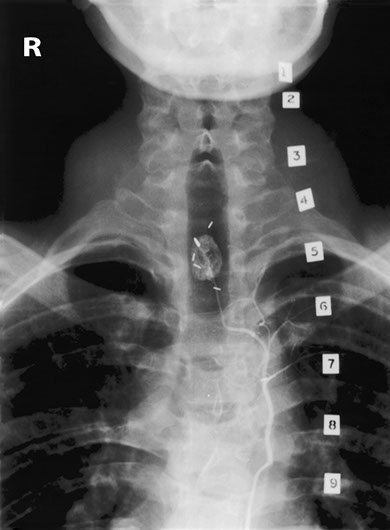

A young man working at the supermarket found his legs becoming weaker and he became unable to push the trolley. A myelogram performed with the help of intrathecal contrast medium demonstrates a tortuous dilated vein flowing along the dorsal aspect of the spinal cord. The conus is dilated, consistent with a syrinx.

A spinal angiogram was carried out. The hairpin bend of the artery of Adamkiewicz was identified in the middle thoracic region and other vessels extending upwards showed a very vascular area at T2. It is important to identify the artery of Adamkiewicz as any fast obstruction of it may lead to infarction in the cord. In many elderly patients the artery is often not found at angiography, presumably due to slow obstruction due to atheroma which can be tolerated.

The small vascular lesion in the lower cervical cord has many small arteries feeding it. and this hyperaemia is responsible for the dilated veins and syrinx.

The patient had a very vascular lesion in the cervicodorsal region consistent with a haemangioma of the cord. The clips are there from past surgical attempts to remove this lesion, but it was impossible to achieve due to rapid bleeding.

In this view we can see the anterior spinal artery flowing beyond the lesion. The patient was hurriedly sent to the operating theater and the haemangioblastoma was successfully removed. The vascularity decreased after embolisation with the patient's own blood clot which inadvertently formed in the catheter.